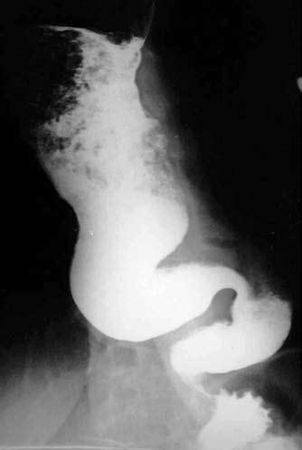

Наиболее трудно отличить начальные стадии инфильтративного рака пищевода в нижнегрудном отделе от кардиоспазма (ахалазии пищевода). Кардиоспазм чаще возникает в более молодом возрасте. Заболеванию больше подвержены женщины, ему нередко предшествует эмоционально-психическая травма. Характерными симптомами кардиоспазма являются дисфагия, боль и регургитация. Дисфагия при этом непостоянна: светлые промежутки чередуются с выраженным затруднением прохождения пищи. Иногда при глотании хуже проходят жидкие пищевые массы (парадоксальная дисфагия). Болезнь длится многие годы. Наиболее информативным в диагностике кардиоспазма является рентгенологическое исследование с использованием контрастной бариевой взвеси. Для этой патологии характерны четкие и ровные контуры пищевода и сохранение эластичности стенок на всем его протяжении. В начале заболевания (I стадия) выявляется временный спазм кардии, с кратковременной задержкой контрастного вещества в кардиальном отделе. Во II стадии болезни определяется стойкий спазм кардии с умеренным расширением пищевода и выраженным нарушением моторики. В III–IV стадиях болезни сужение кардиального отдела стойкое и значительное. Сочетание существенного расширения пищевода, до 6–8 см и более, с S-образным искривлением пищевода, характерным сужением кардии в виде "мышиного хвоста" или "писчего пера" и отсутствием "газового" пузыря желудка является типичной рентгенологической картиной кардиоспазма (рис. 43).

Рис. 43. Кардиоспазм. На рентгенограмме ниже места резкого расширения определяется нитевидное сужение просвета в виде "мышиного хвоста". Тотчас ниже диафрагмы слева в дне желудка газовый пузырь не определяется